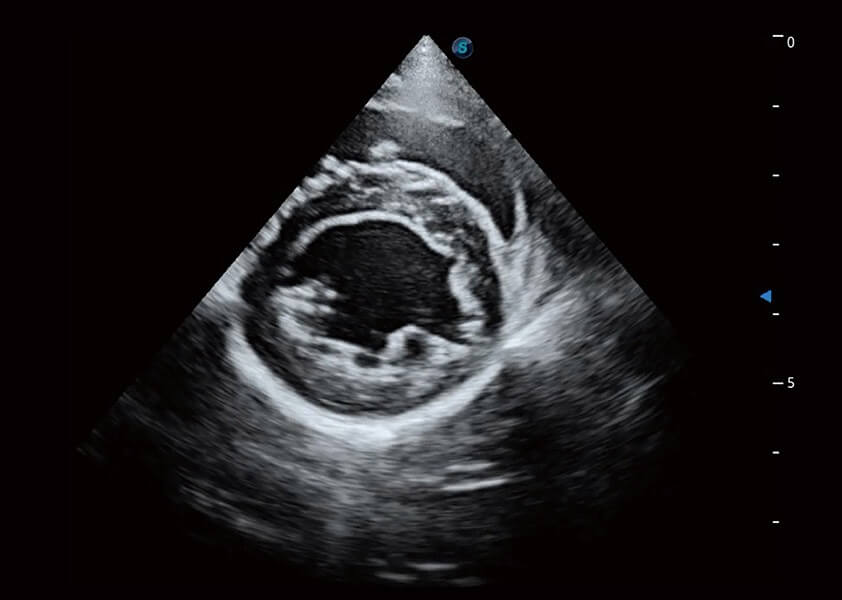

ProPet 60 作为一款高端台式动物超声设备,为动物医生的日常诊断提供了一系列贴合动物临床需求、解决临床实际问题的高级成像功能。凭借全系列高清探头,满足医生对腹部、心脏、生殖、浅表、肌骨等成像的所有需求,切实帮助您提升检查效率,提高诊断信心。

兽用彩色多普勒超声诊断系统

动物是人类最亲密的朋友和最值得信赖的伙伴。云顶集团官网也一直致力于探索动物专用的超声影像解决方案。 全新推出的ProPet系列,是云顶集团官网在动物超声影像智能化、专业化、精准化的一次跨越式革新。动物不能用言语来表述自己的不适,通过超声影像,ProPet系列搭建了动物医生与不同物种沟通的“桥梁”,为动物医生注入了“治愈之力”。